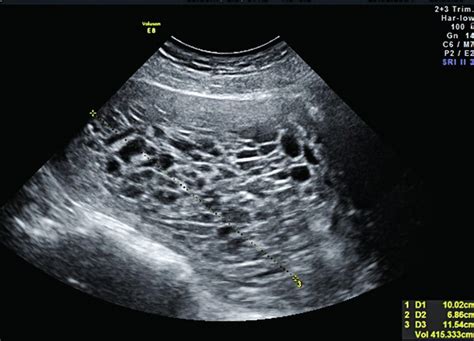

K nepravidelnému vývinu plodových obalov a plodu patrí: Mola hydatidosa - zásneť hroznová

Mola hydatidosa je ochorenie trofoblastu, pri ktorom okraje placenty vytvoria tvary malých hroznových vačkov. Zvyčajne sa celá dutina maternice vyplní cystami a embryo zaniká. Mola môže byť bez prítomného plodu alebo len čiastočná, pri ktorej sa plod vyvinie len neúplne.

Ako sa prejavuje mola?

Porucha sa zvyčajne prejaví v 3. mesiaci tehotenstva a môže sa prejavovať ako:

- Špinenie alebo krvácanie, niekedy s kŕčmi.

- Vylučovanie cýst.

- Rýchly rast maternice.

- Neprítomnosť srdcovej aktivity plodu.

- Vysoký krvný tlak.

- Príliš vysoká hladina HCG.

- Pri ultrazvukovom vyšetrení nie je plod prítomný.

Mola sa odstraňuje kyretážou a hodnoty HCG sa sledujú po dobu jedného roka, aby sa vylúčili zvyšky moly v maternici.

Mimomaternicové tehotenstvo vzniká, ak sa oplodnené vajíčko uhniezdi mimo maternice, najčastejšie vo vajíčkovode. Je to život ohrozujúci stav pre ženu. Pri sonografickom vyšetrení nie sú viditeľné známky gravidity v maternici, ale môžu byť prítomné vysoké hodnoty HCG a zhrubnutá sliznica maternice.